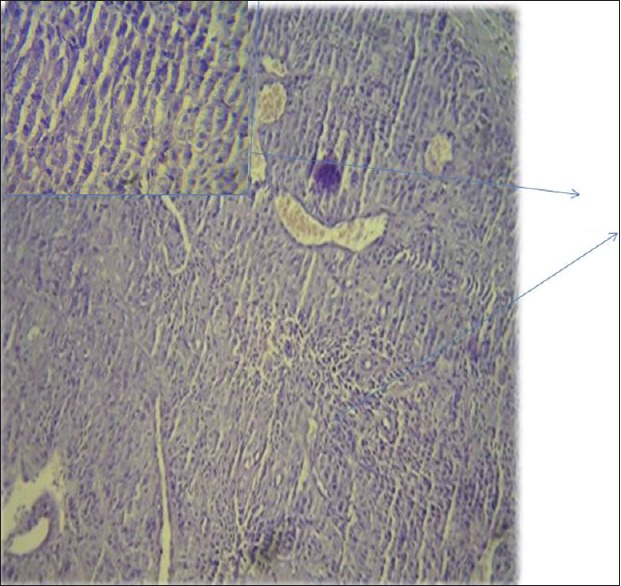

Further evaluation was carried out with imaging of chest and abdomen, along with imaging of referable sites. Contrast-enhanced computed tomography (CECT) chest and abdomen was carried out in all patients, revealing right hilar mass in 66% of patients, left hilar mass in 22%-of patients, and 12%-had right peripheral lung mass. Superior vena cava (SVC) partial or complete occlusion was seen in 33%; right-sided plural effusion, ascites, and liver metastasis was seen in 11%-each [Figures [Figures11 and and2].2]. Bronchoscopy revealed intrabronchial pathology and clinched the diagnosis in 88% of patients; rest of patients needed computed tomography (CT)-guided biopsy of lung for getting histological diagnosis. Lung biopsy was positive for napsin, cytokeratin (CK) 5/6, and negative for synaptophysin and thyroid transcription factor 1 [Figure 3]. Bone scan was positive in two patients with one uptake in iliac bone and other in Tibia [Figure 4 of X-ray Tibia]. CECT of muscle metastasis sites was done and biopsy was carried out in each patient [Figure 5]. Distribution of metastasis was unique, 66%-patients had pelvic skeletal muscle involvement, 22%-had thigh muscle, and 11%-had lower paraspinal muscle metastasis.

| Figure 3:Histopathology showing squamous cell carcinoma of lung